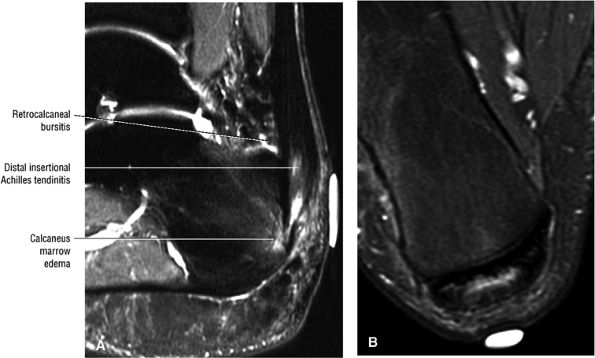

Haglund's deformity represents insertional tendinitis with a posterosuperior calcaneal bony prominence and retrocalcaneal tendo Achilles bursitis.

Haglund's deformity (Figs. 5.115, 5.116, and 5.117) (insertional tendinitis with reactive calcaneal marrow edema [see Fig. 5.116], and the constellation of thickened tendon, retrocalcaneal/tendo Achilles bursitis, and a calcaneal bony prominence)

FIGURE 5.108 ● Insertional tendinitis with hyperintensity of the thickened distal Achilles tendon. Retrocalcaneal bursal inflammation and calcaneus marrow edema are shown. In contrast to non-insertional degenerative tendinosis, the process of insertional Achilles tendinitis demonstrates an inflammatory process histologically. Achilles enthesopathy is another term for insertional Achilles tendinitis. FS PD FSE (A) sagittal and (B) axial images.

FIGURE 5.115 ● The retrocalcaneal bursa is located between the Achilles tendon and the posterosuperior calcaneal prominence. The adventitial bursa or tendo-Achilles bursa is located between the Achilles tendon and the skin. Lateral color graphic.

FIGURE 5.116 ● Haglund's deformity with distal Achilles tendinitis, osseous edema of the posterosuperior calcaneus, and visible fluid and/or thickening in the retrocalcaneal bursa and tendo-Achilles bursa. (A) Lateral color illustration. (B) Sagittal FS PD FSE image.